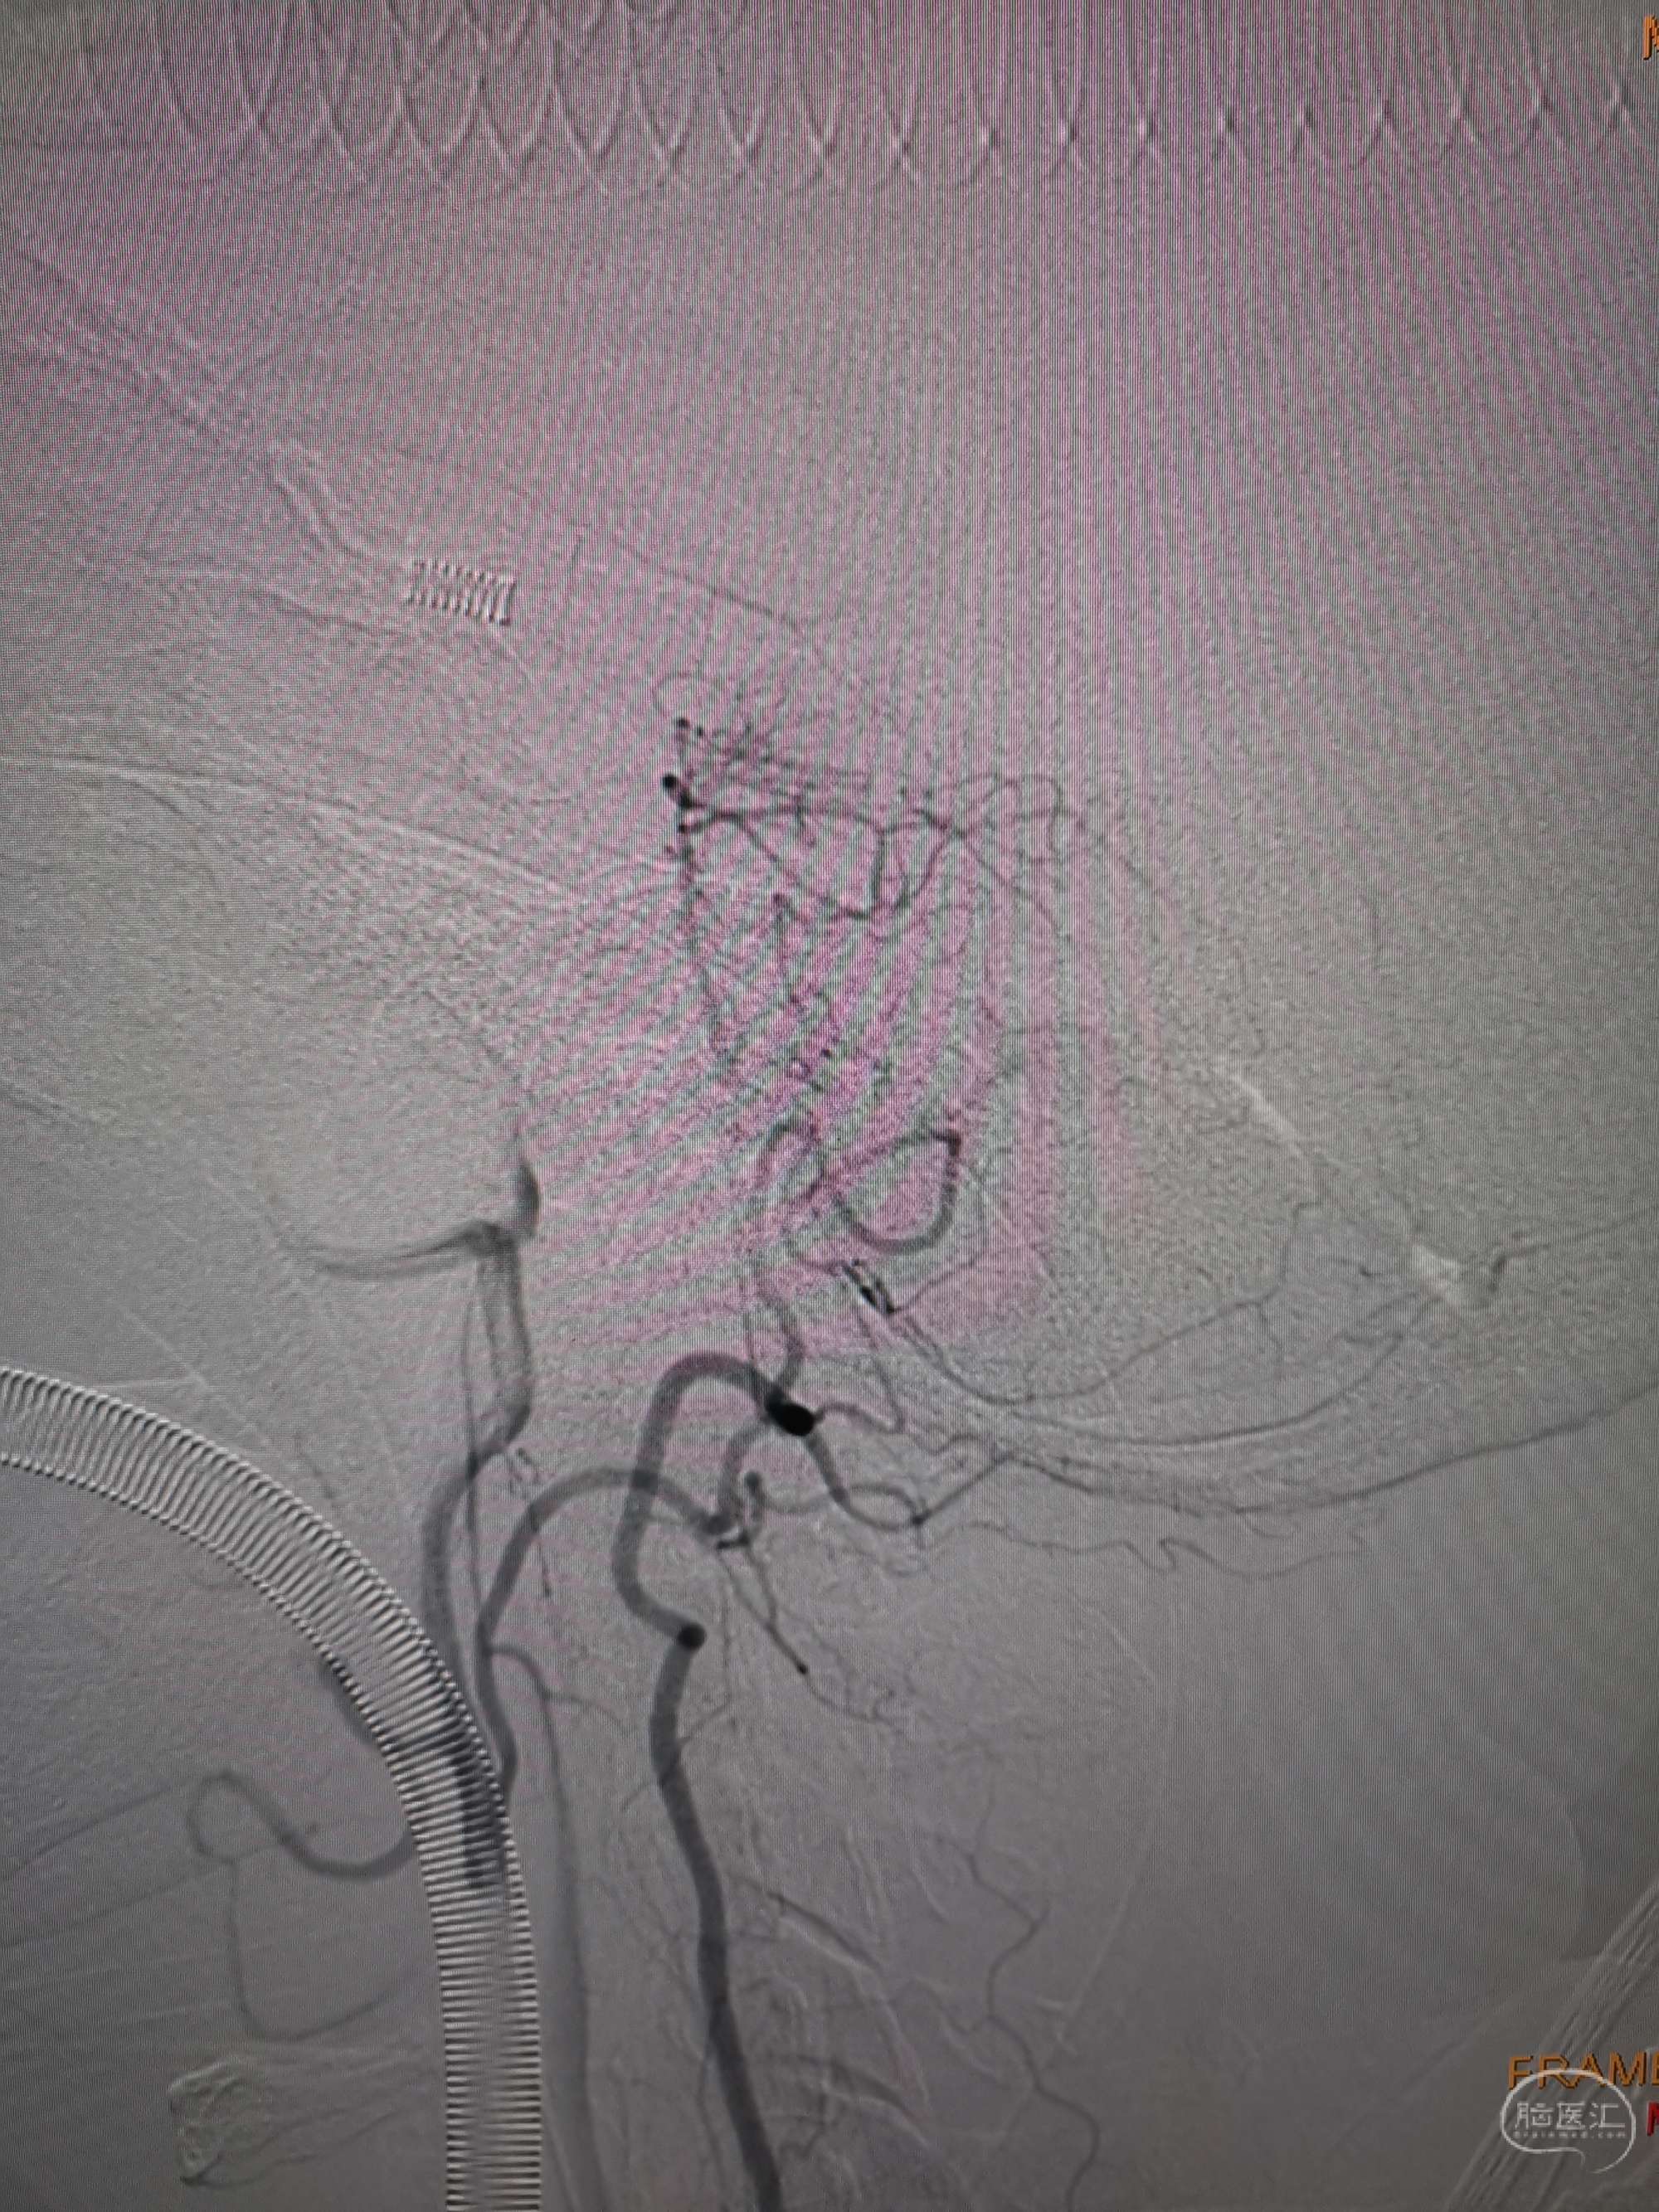

术后造影见左侧椎动脉闭塞段管腔恢复正常直径,远端血运良好。